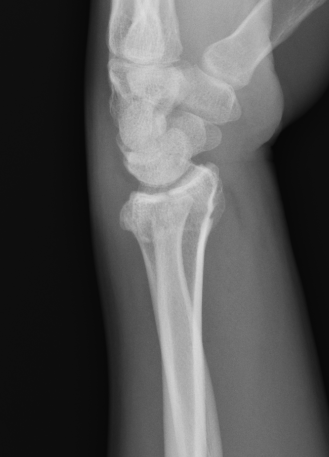

Smith's Fracture

- distal radial fracture with volar displacement

- need long arm cast in supination

Distal Radius Smiths Fracture